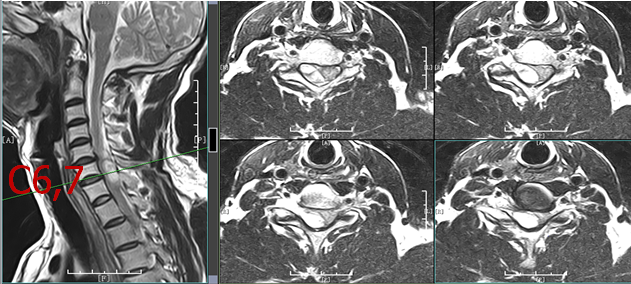

颈椎MRI